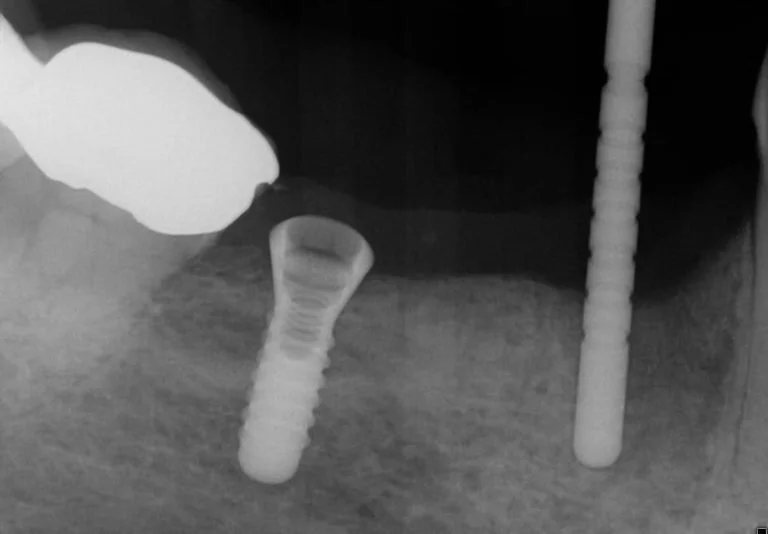

Diagnostic pre-treatment image 1

Due to the extent of the infection, tooth 44 was extracted, the site carefully curetted, and then left to heal for three months prior to bone volume assessment with a cone beam tomograph (Soridex).

Once healing and adequate bone volume above the mandibular canal had been confirmed, two Bioconcept 3.3mm x 10mm tissue level implants were placed in sites 44 and 46. Several careful progressive intraoperative periapical radiographs were taken to confirm vertical position relative to the mandibular canal. Both implants were then placed with a primary stability of over 30 Ncm as a one stage surgical procedure, and 2mm healing abutments were then secured.